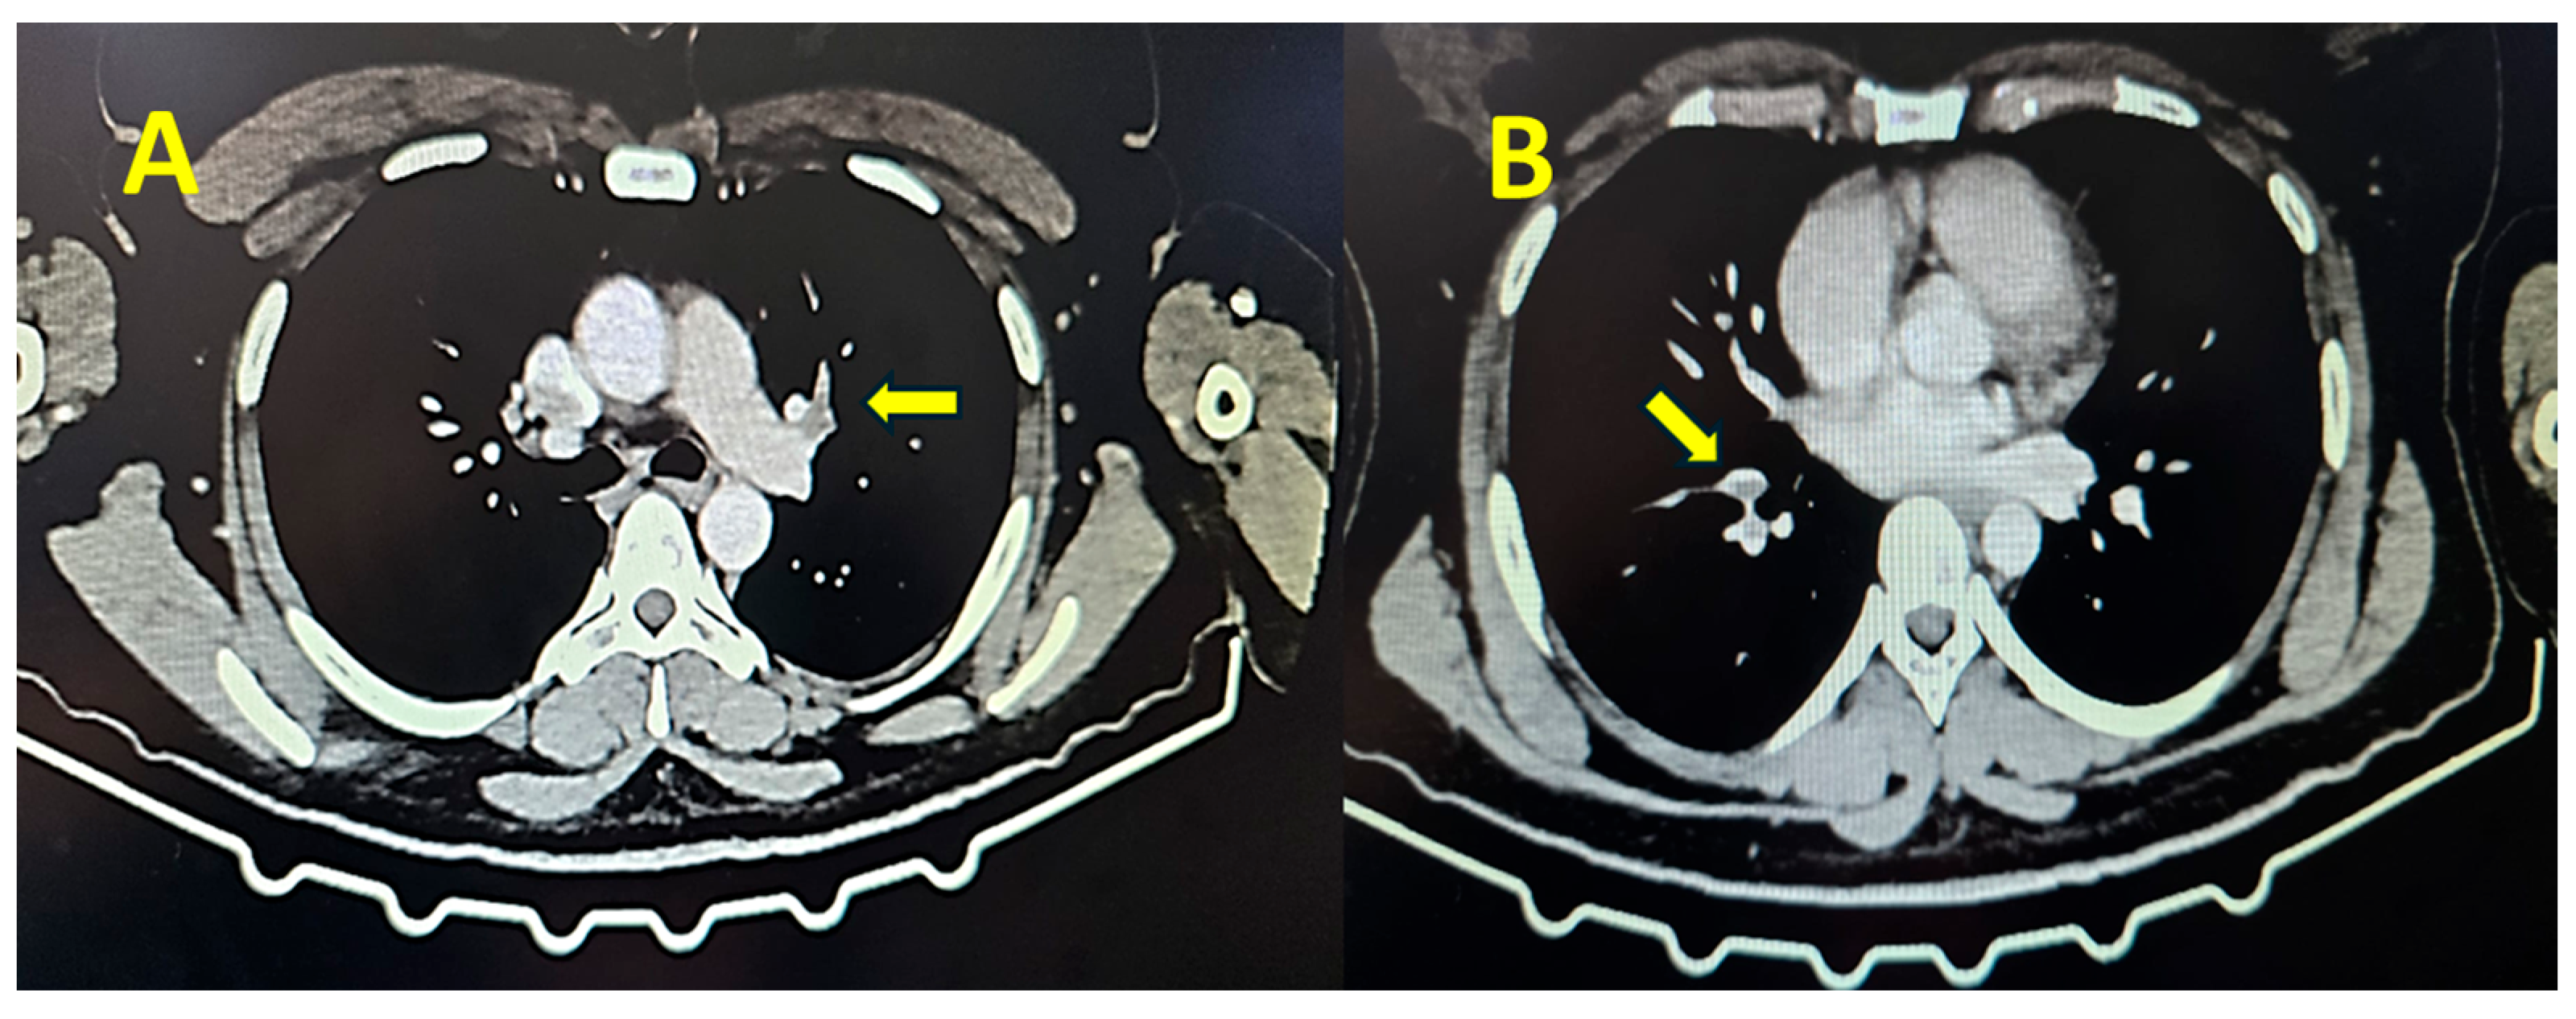

Contrast thoracic computed tomography showed the presence of thrombi in the pulmonary artery, establishing the diagnosis of pulmonary embolism (Figure 1).

Figure 1. Contrast thoracic computed tomography showing the presence of thrombi at the bifurcation of the left pulmonary artery (A, yellow arrow), right superior lobar artery, and segmental arteries (B, yellow arrow).